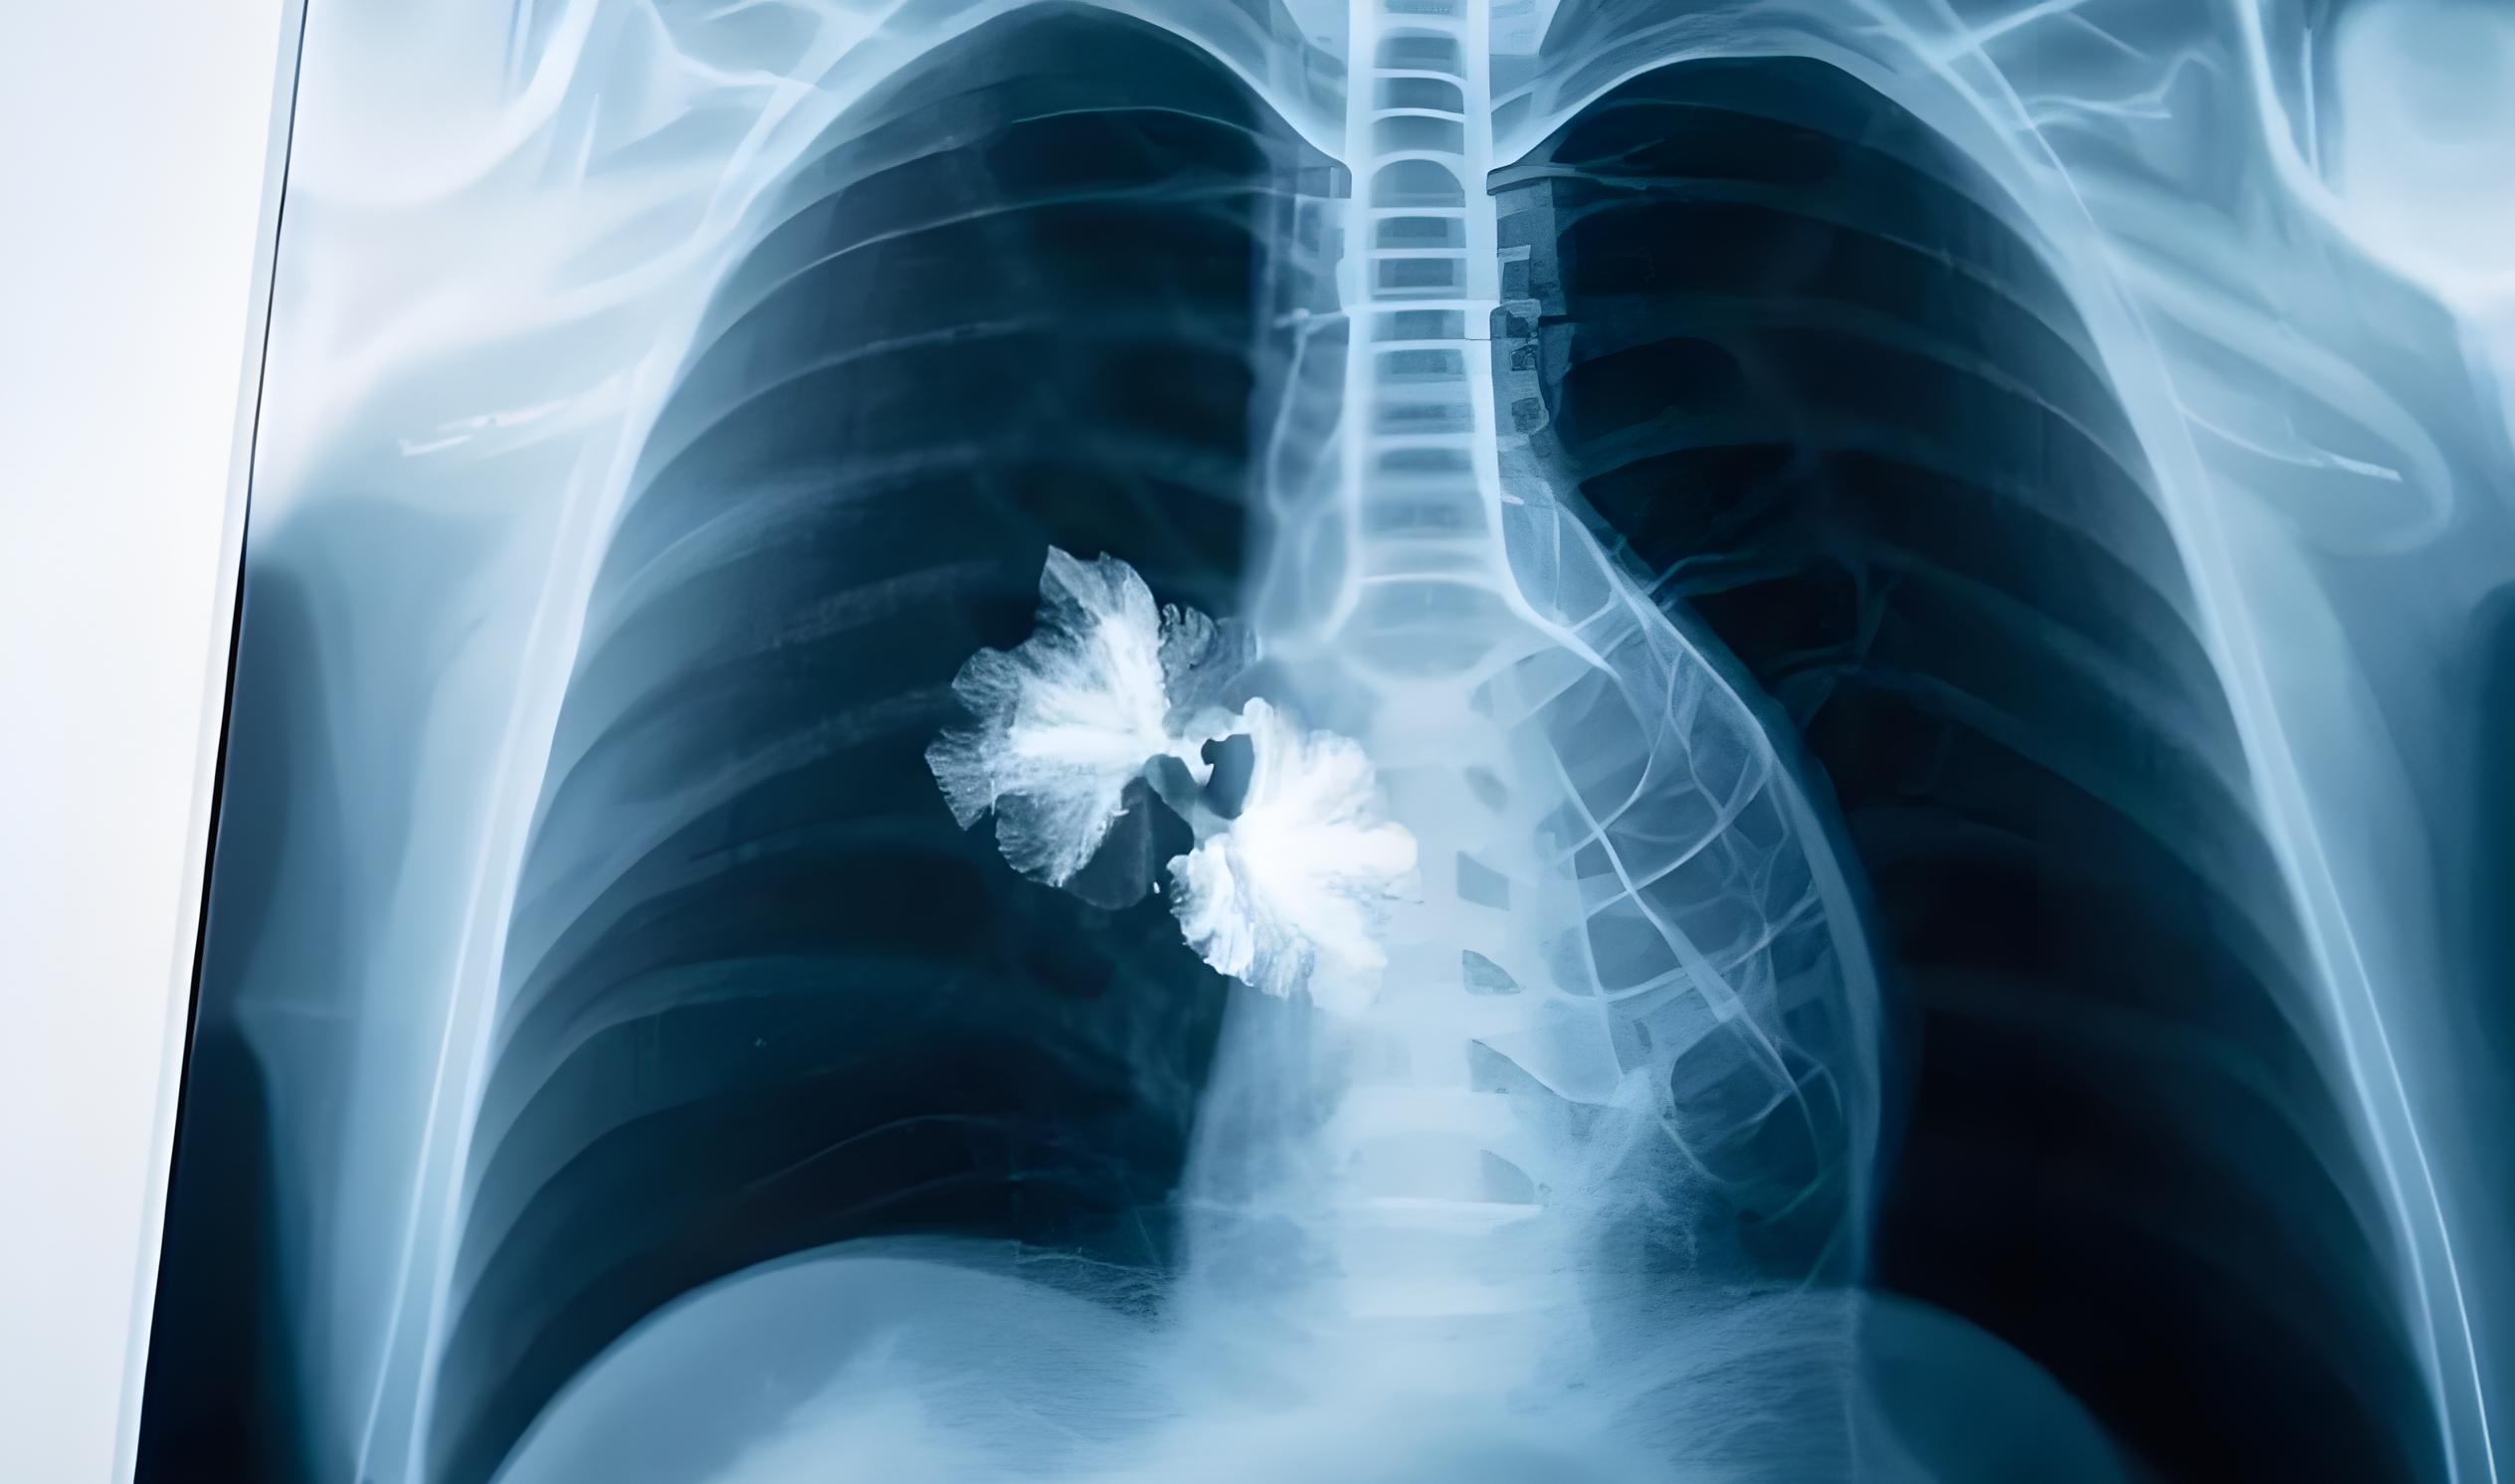

?近年來,肺結節問題愈發嚴峻,已成為全球矚目的公共健康難題。